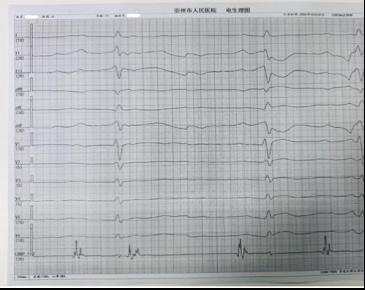

手术团队分两步精准构建了生理性起搏体系。首先成功行右心室左束支区域起搏(详见图2),使 QRS 波宽度缩至 93ms(达到健康人群正常范围),确保左右心室同步收缩,避免传统右室心尖起搏导致的心室不同步问题;随后团队将心房电极精准植入Bachmann束区域成功行Bachmann 束起搏,起搏时见P 波时限更高更窄(P波由 119ms直接缩短至 100ms,P波高度增加(详见图3、图4)。

图2:左束支区域起搏 图3 Bachmann 束起搏 图4 Bachmann 束电位

相较于传统起搏技术,该方案的优势集中体现在左束支区域起搏的基础上进一步实现了 Bachmann 束起搏:一方面,可显著降低术后房颤发生率(房颤是传统起搏患者常见远期并发症);另一方面,避免了传统右心耳起搏可能带来的右心耳穿孔、血栓形成等潜在风险,安全性与生理性兼具。

术后,患者心动过缓症状彻底改善,气短、乏力等不适消失,心功能逐步恢复。这得益于全生理性起搏的获益,更重要的是带来的心房同步传导,心室同步收缩,这大幅降低了她未来发生心衰、房颤的风险,为其后续高质量生活提供了 “心” 保障。

此次全生理性起搏手术的成功,核心在于Bachmann束起搏技术与左束支区域起搏技术的创新性联合应用。这一突破性实践,不仅打破了传统起搏“仅保证心跳,不追求同步”的局限,更实现了“让心脏跳起来,更让心脏跳得自然、跳得协调”的生理性治疗目标。